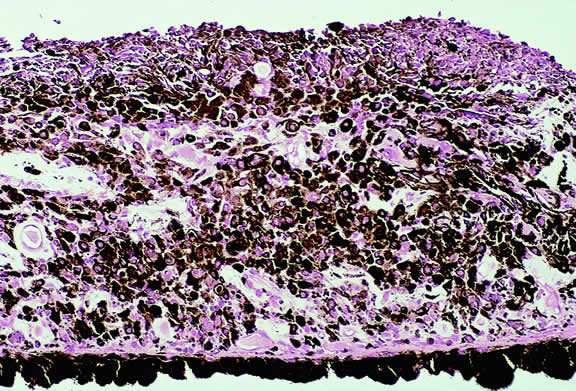

The substrate for the development of melanoma in white patients with ocular melanocytosis is a diffuse nevus that affects all, or part, of the uveal tract. Clinically, the nevus typically is evident as hyperchromic heterochromia iridum, patchy slate gray epibulbar pigmentation, and a darker aspect of the fundus compared with the fellow eye (Fig. 8). A sector of uvea is affected in some patients, however, and the nevus may spare the iris. The uvea in congenital melanocytosis is thickened by an increased number of heavily pigmented nevus cells similar to those found in melanocytomas (Fig. 9). RPE abnormalities such as drusen often develop on the surface of the thickened choroid.48 The sclera also contains patchy foci of pigmentation. The slate gray conjunctival pigment reflects the presence of dendritic melanocytes on the epibulbar tissues deep to the conjunctiva. Nevus of Ota does not predispose to conjunctiva melanoma. However, patients rarely may develop melanomas of the orbit49–51 and even leptomeninges.1,52,53 White patients who have congenital ocular or oculodermal melanocytosis should be followed periodically because of the increased risk of uveal melanoma.54

Fig. 9. Congenital ocular melanocytosis, choroid. Choroidal stroma is thickened by infiltrate of heavily pigmented benign melanocytes. Patient had iris heterochromia and skin pigmentation consistent with nevus of Ota. (Hematoxylin-eosin, × 100.)